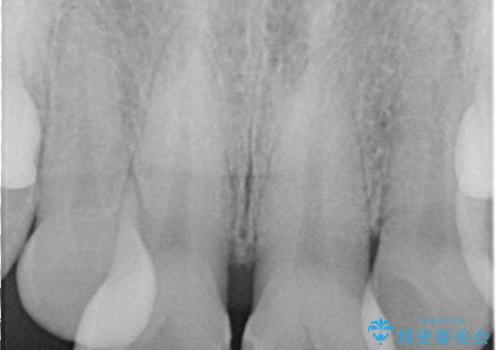

上下ともに軽度の叢生があり、下顎がやや前突傾向にあったため、本来であれば矯正治療が第一選択となります。矯正によって下の前歯を後方に移動させることで、咬み合わせの改善とともに前歯のデコボコも整えることができます。

そのため今回は、右上2番を抜歯し、右上1番および左上1番をオールセラミッククラウンで審美的に修復しました。

上下に叢生(歯のデコボコ)と反対咬合があるため、本来であれば矯正治療が最も理想的な治療選択となります。